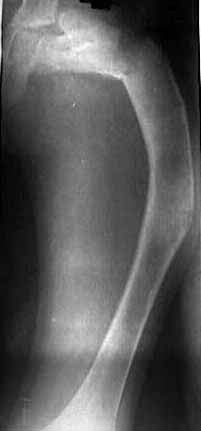

I did not have Zickel nail so planned for Gamma. Had to open the fracture site as could not reduce it closed. Also did a wedge osteotomy in mid shaft level to correct the deformity. The wide canal diameter allowed me to pass the straight nail down the canal. The thigh is now straight, leg length almost equal ( affected leg is probably 1/2 cm longer !) and no neurovascular deficit.

The patient is delighted and working hard on knee flexion and has acheived up to 90 degrees now. Histopathology has come back as fibrous dysplasia. I am attaching the pre op and post op xrays.

The Xrays look good but clinically patient has gross limp. With the straightening of femur the leg lengths are almost equal ( Affected leg is about 1/2 cm longer). But he has about 40 degree of fixed abduction deformity in the affected leg so when he stands the pelvis tilts and he has apparent lengthening of about an inch on the affected leg. This makes him limp. The abduction deformity is probably secondary to contracture of the Gluteal muscles. The question is whether I should release them now or will they stretch out in time.